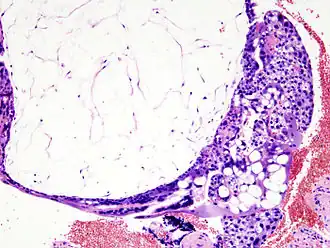

![]() Corte histológico de una mola hidatiforme teñido con hematoxilina y eosina. Se ve una vellosidad de gran tamaño llena de líquido, con proliferación de células en el trofoblasto que lo rodea visibles como numerosos núcleos violeta. | ||